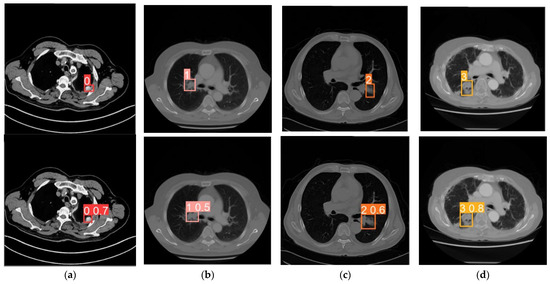

4.5. Experimental Results Visualization